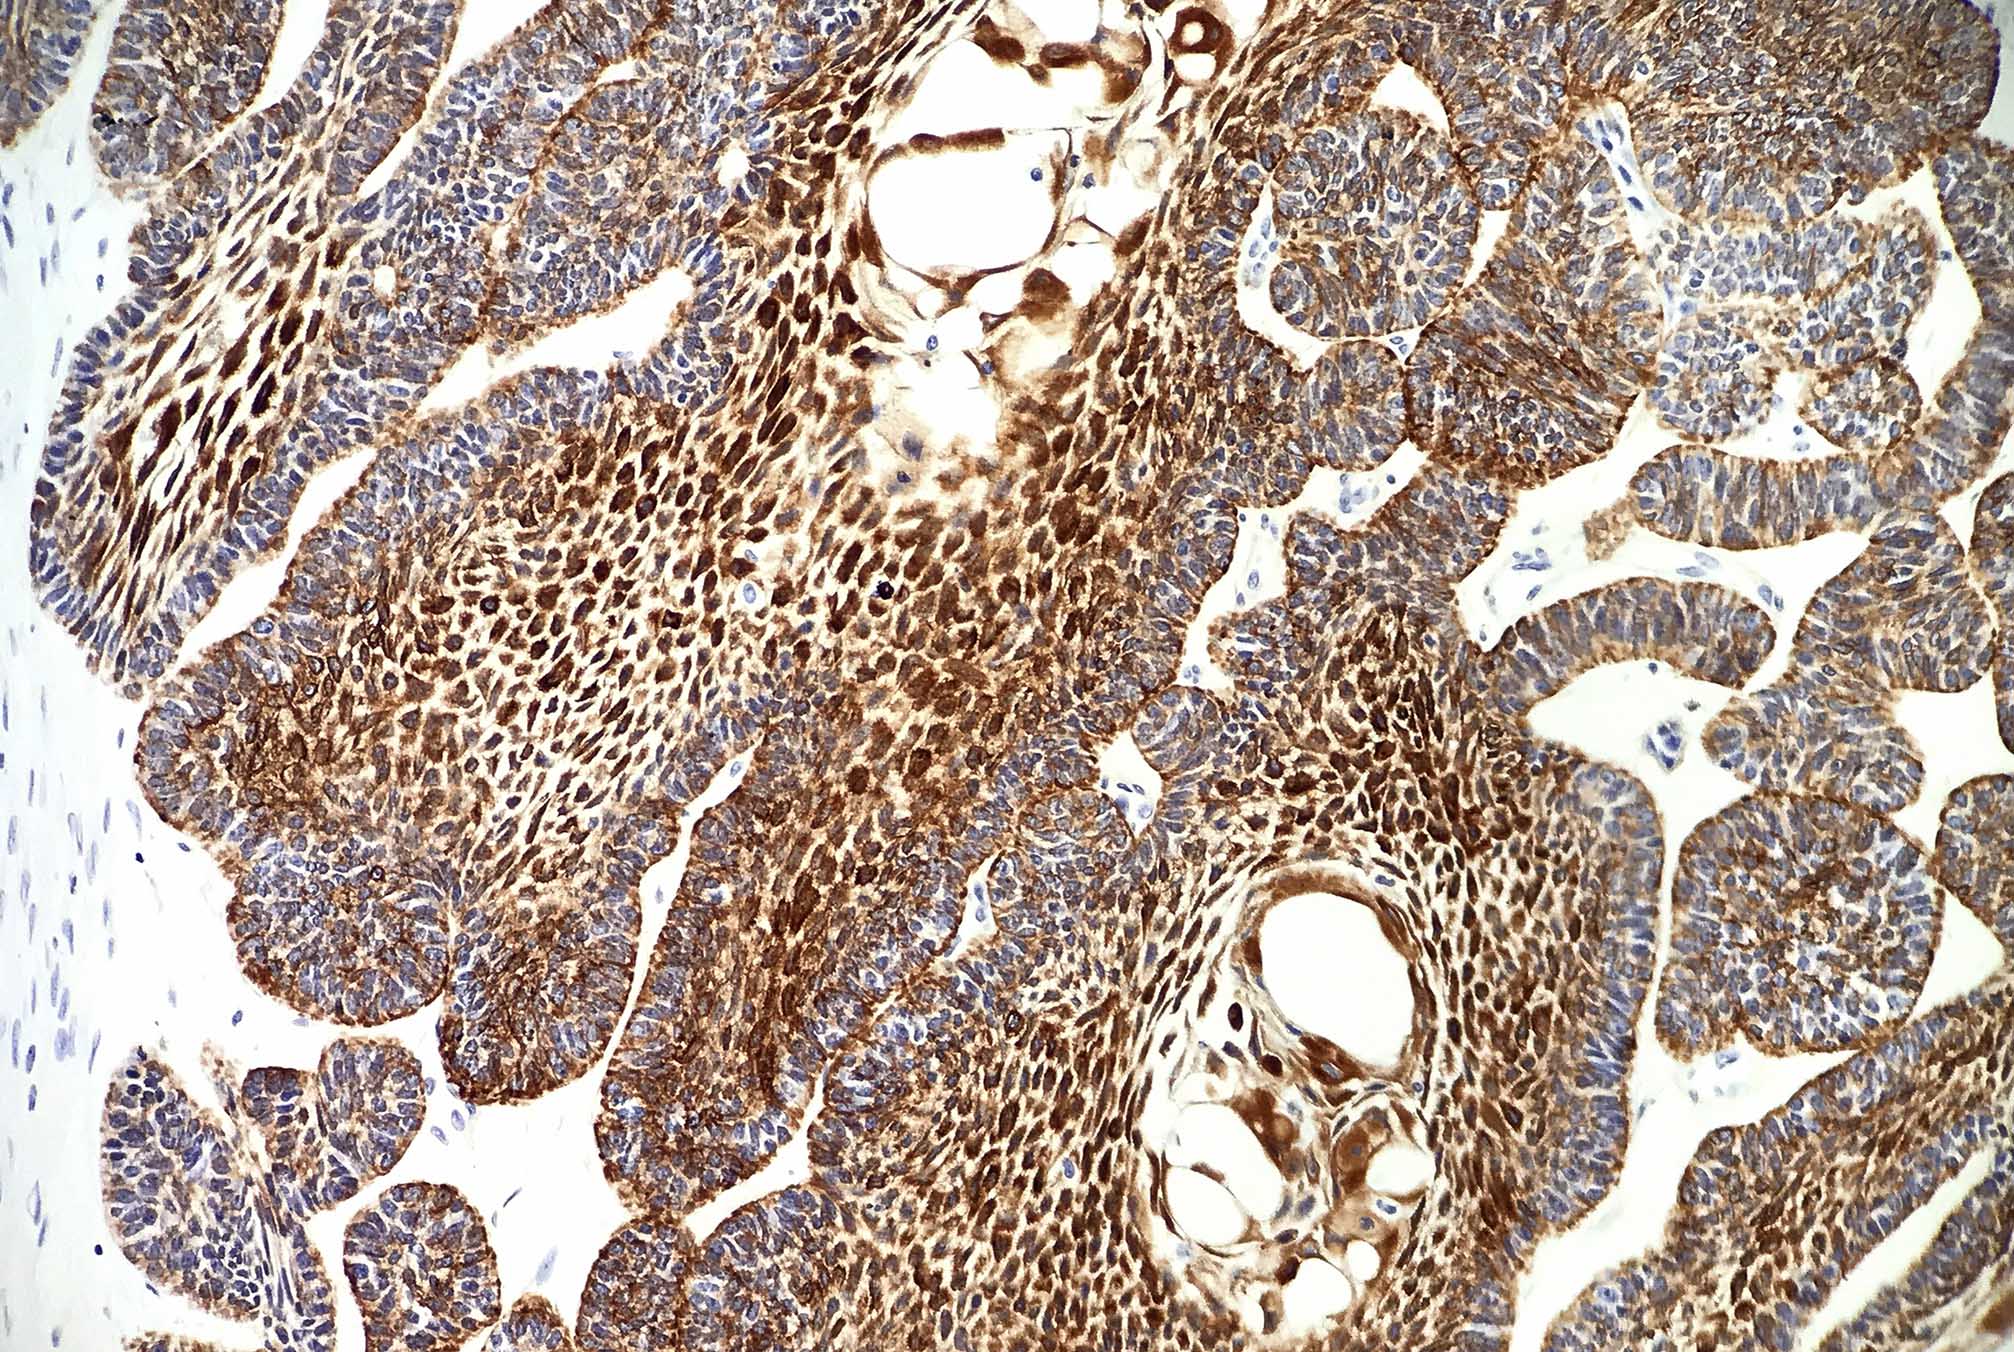

Microscopic (histologic) images

Contributed by Kelly Magliocca, D.D.S., M.P.H. and Anne C. McLean-Holden, D.M.D., M.S.

Microscopic (histologic) description

- Within the epithelial islands and cords of conventional ameloblastoma and the cystic epithelial lining of unicystic ameloblastoma, the odontogenic epithelium shows similar changes:

- Columnar cells with hyperchromatic nuclei at basal layer, exhibiting peripheral palisading

- Cells show reverse polarization away from basement membrane (Vickers-Gorlin change)

- Subnuclear vacuolization

- Suprabasal cells with a loose, network-like arrangement, recapitulating stellate reticulum formation seen in normal odontogenesis

- Ameloblastoma, conventional type has at least 6 histopathological patterns

- Plexiform: cords and sheets of anastomosing odontogenic epithelial cells; classic peripheral palisading and reverse polarity not always obvious